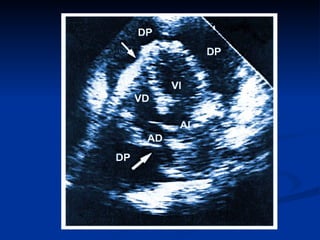

TAPONAMIENTO CARDIACO: SIGNOS ECOCARDIOGRAFICOS Cambios respiratorios anormales en las dimensiones  ventriculares  durante el ciclo respiratorio. Colapso de AD y VD. Colapso de cavidades izquierdas. Dilatación de VCI con ausencia de variaciones respiratorias. Variaciones respiratorias exageradas en los flujos mitral, aórtico y  tricuspídeo.

TAPONAMIENTO CARDIACO: SIGNOSECOCARDIOGRAFICOS Cambios respiratorios anormales en las dimensiones ventriculares durante el ciclo respiratorio. Colapso de AD y VD. Colapso de cavidades izquierdas. Dilatación de VCI con ausencia de variaciones respiratorias. Variaciones respiratorias exageradas en los flujos mitral, aórtico y tricuspídeo.